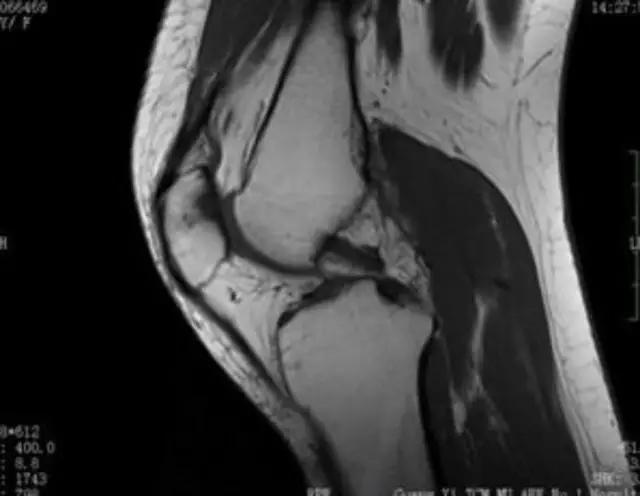

下图是同一个病人的MRI照片,MRI显示的内容更多,包括骨与软组织等,很多早期的、细微的病变都能清晰显示,其诊断报告对病人造成的影响也更大!

我们可能都不熟悉T1、T2,怎么办?当我们发现有问题后,利用照片上图像的对比,推测病变的可能也是一种诊断方法。病例:黄XX,女,39岁,左膝关节反复交锁1年。图1:肿物信号与骨信号一样图2:肿物信号与骨信号一样图3:肿物信号与骨信号不一样 肿物应该与骨相关,但不是骨性,推断:膝关节滑膜软骨瘤。手术后得到证实。